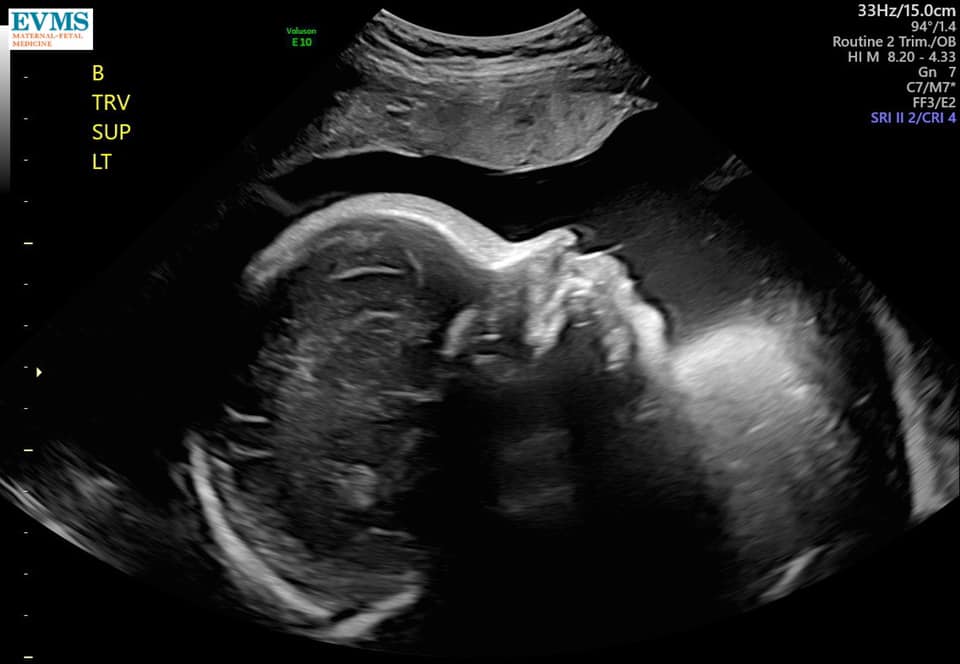

Ultrasound Photos at 32 Weeks Pregnant With Twins